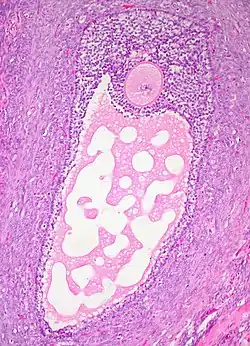

![]() Histology section of a mature ovarian follicle. The oocyte is the large, round, pink-staining cell at top center of the image. | |